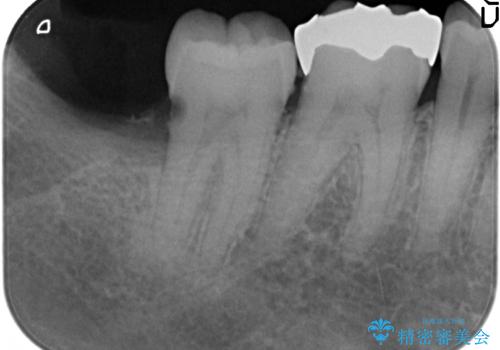

- 右下奥歯がたまにしみるので診て欲しいといらっしゃった方の症例です。

右下7番目の歯の歯茎より深い位置に虫歯があったため、親知らずを抜歯後PGA(ゴールド)インレーによる修復を行いました。